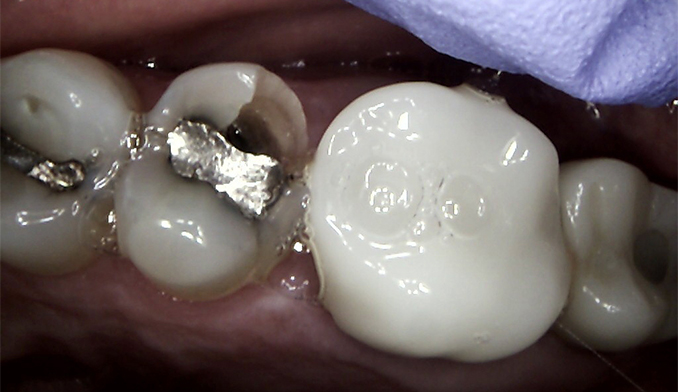

Same-Day Crown Replacement for Lower Molar

The patient’s old crown on the lower right molar came off and needed replacement. We created and cemented a new crown within a two-hour appointment, restoring the tooth’s function and appearance in one visit.